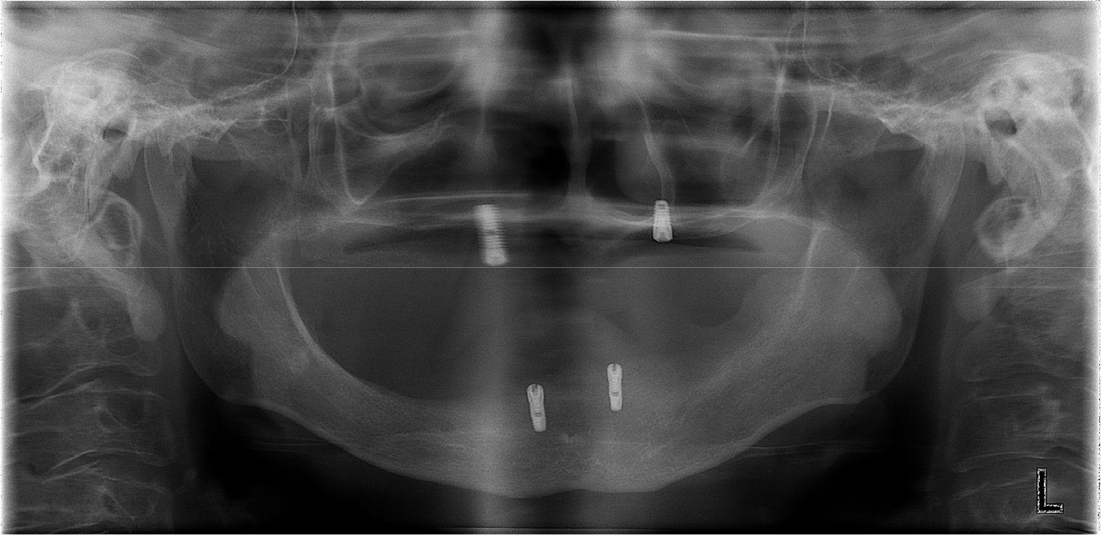

Postoperatively, the maximum mouth opening was increased from 12 to 35 mm, and the oral commissure was enlarged. After 2 months of recovery, temporary complete upper and lower dentures were delivered to the patient (Fig. 6). On January 19, 2011, two implants were placed in each arch under general anesthesia (Fig. 7). A panoramic radiograph revealed four implants (Fig. 8). At the Department of Prosthodontics, magnet-attached overdentures were fabricated and delivered 6 months after implant installation (Fig. 9). Vestibuloplasty creates a larger surface area for better denture adaptation. The patient was followed-up for 11 years without any complications (Fig. 10).